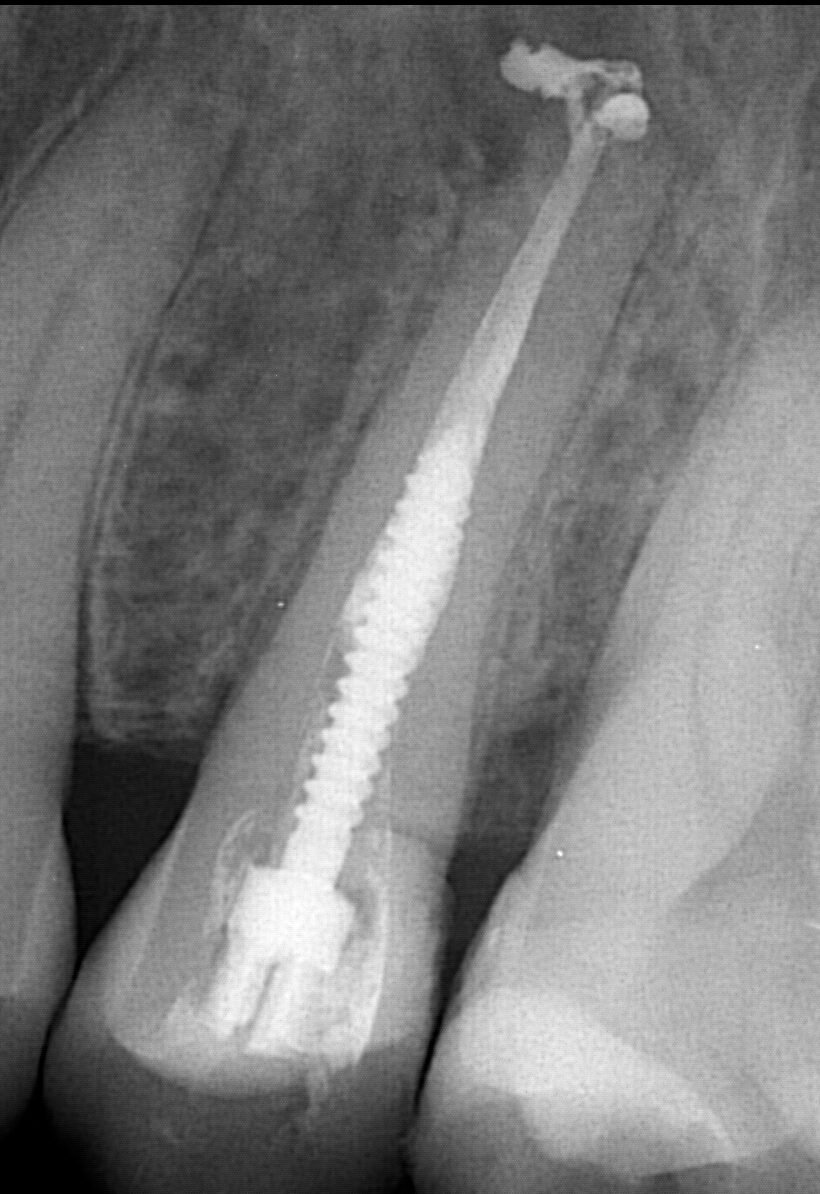

Il sera important que dans votre sélection de patient, vous nous transmettez toutes les infos par courriel (radios, cas cliniques, histoire médicale). Que vous avisiez vos patients qu’ils devront se mettre disponibles pour ces deux dates-là et que lorsque les inscriptions seront fermées, nous ferons la cédule des chirurgies.